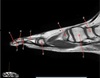

25

What is letter C?

SUPRASPINATUS MUSCLE

26

What is letter D?

ACROMION

27

What is letter E?

SUPRASPINATUS TENDON

28

GREATER TUBEROSITY

29

What is letter G

SCAPULA

30

What is letter A?

CLAVICLE

31

What is letter B?

AC JOINT

32

33

BICEPS TENDON

34

35

STERNOCLAVICULAR JOINT

36

STERNAL NOTCH

37

VERTEBRAL BODY

38

RT LUNG

39

What is letter F?